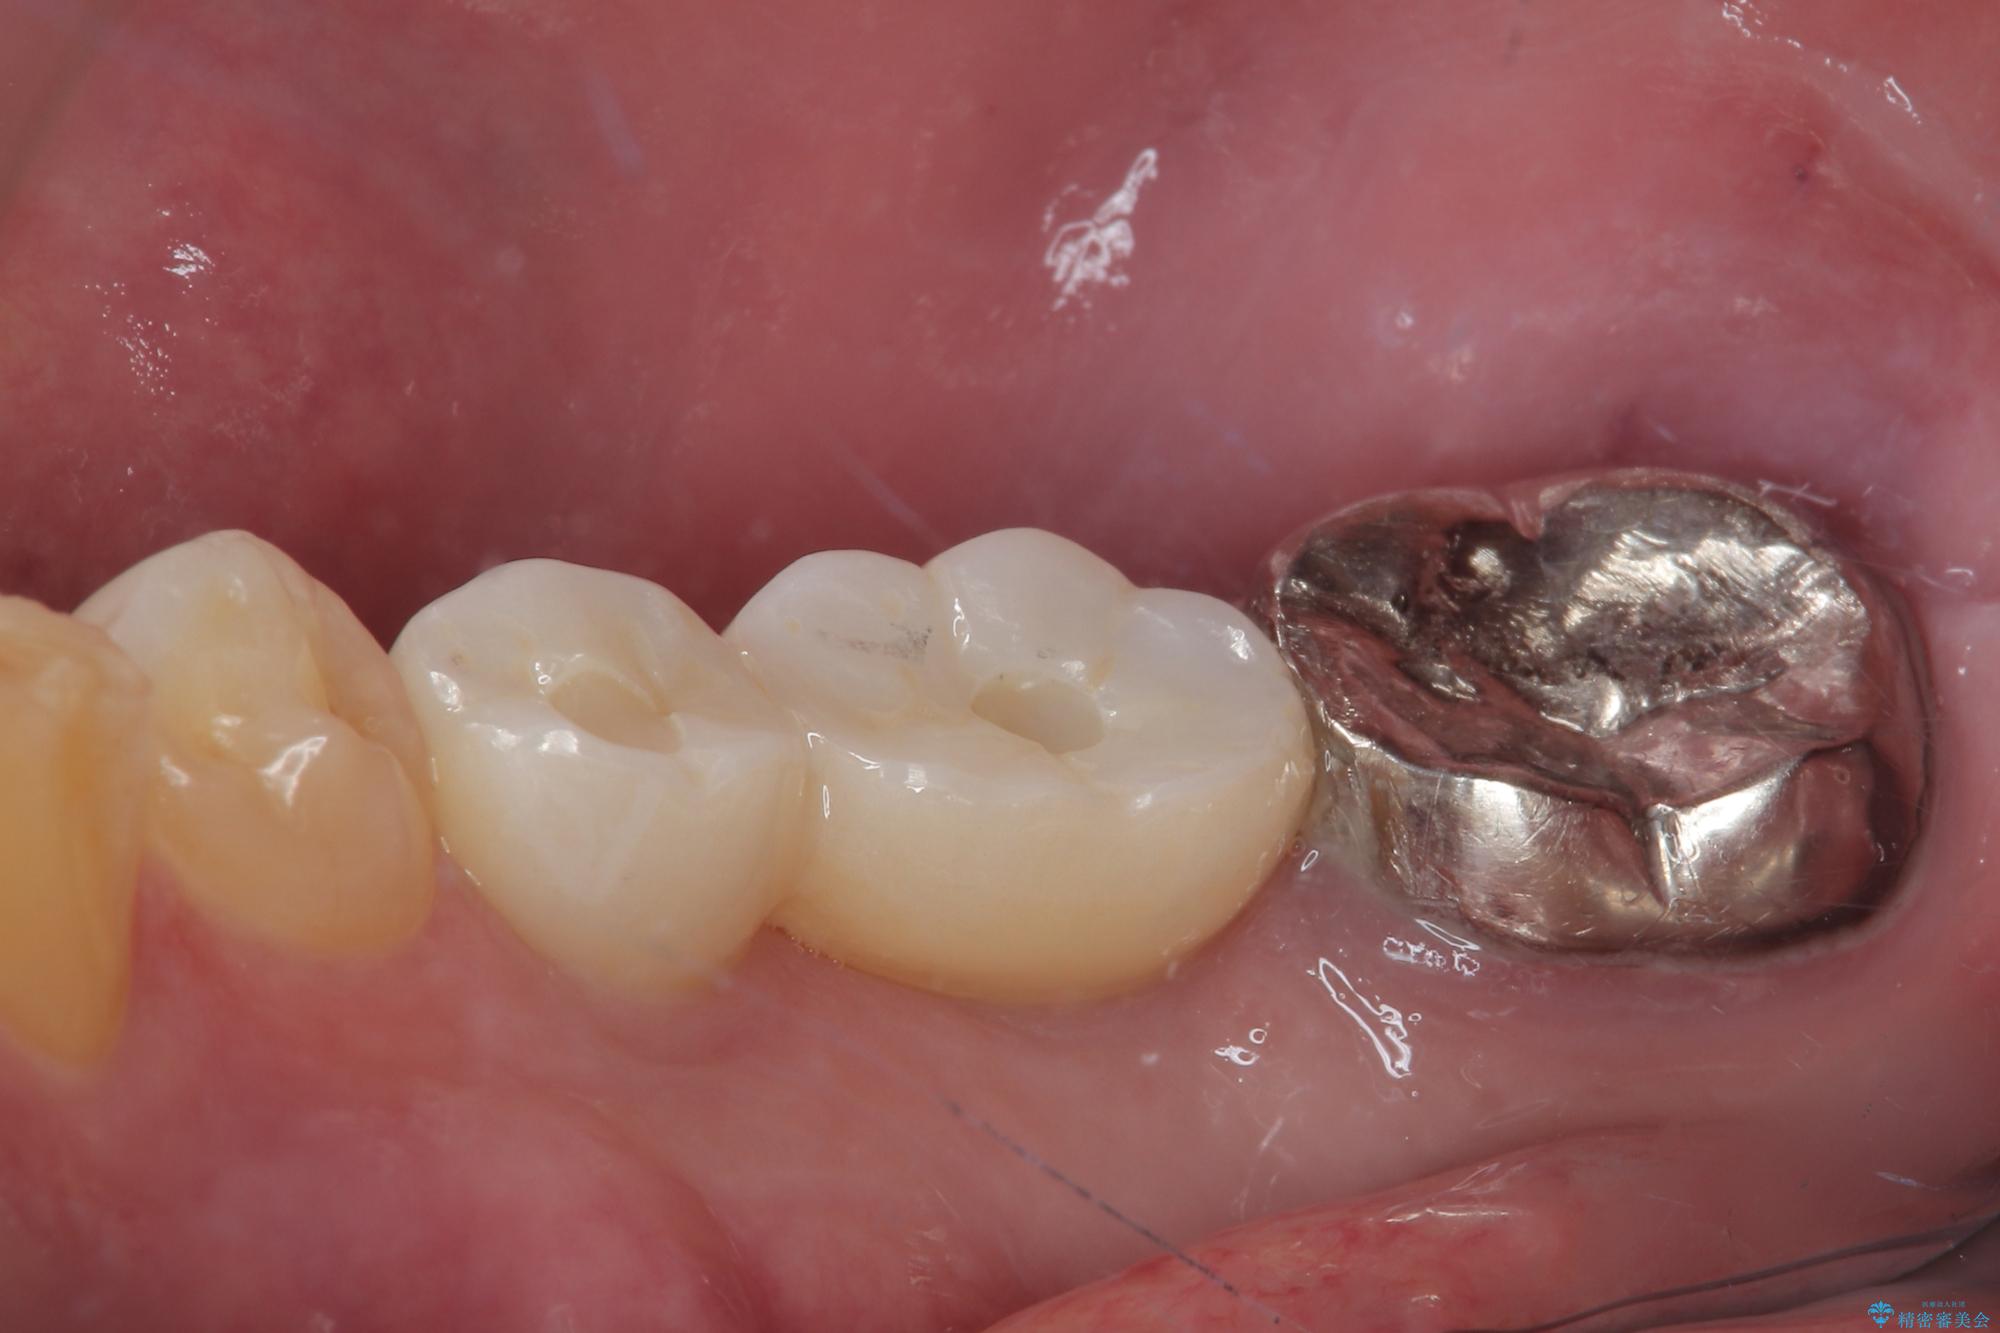

- むし歯を放置したことで、歯茎で膿が腫れ上がったしまったとのことで来院された患者様です。

ブリッジの支台歯が痛みを覚え、近医でブリッジを切断してもらって以降、そのままにしてしまったとのことでした。

問題が起きていた手前の歯から膿が出てきたことを自覚して当院を来院されましたが、既に歯根破折をしており、抜歯が必要な状態でした。